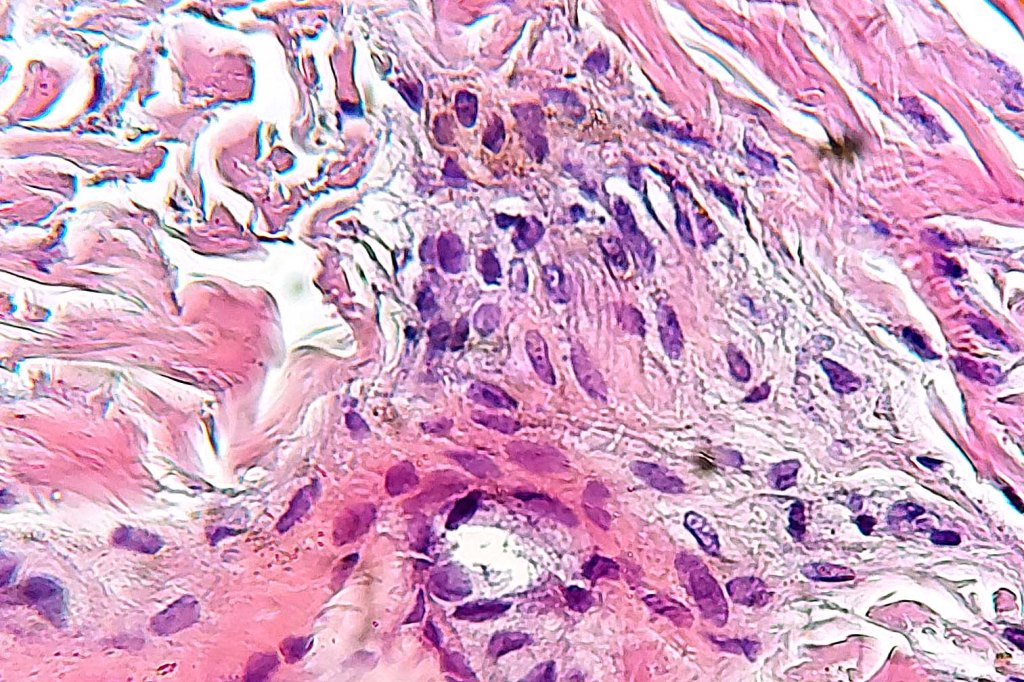

Histologically, both lesions are characterized by the presence of denritic melanocytes in the upper & mid dermis. The overlying epidermis is often hperpigmented and increased numbers of melanocytes are sometimes evident.

Histologically, it is characterized by a dense population of spindled, dendritic melnanocytes & melanophages with variable fibrosis. It may sometimes represent a component of a combined nevus. Mitotic activity is not usually present and pleomorphism is absent (see atypical blue nevus below). Involvement of the arrector pili muscle is not uncommon.

•Admixture of spindle cells, pigmented bipolar or dendritic cells & melanophages

•Cytoplasm is pale and nuclei are small with inconspicuous nucleoli

•An alveolar pattern is characteristic particularly with clear cell nodules